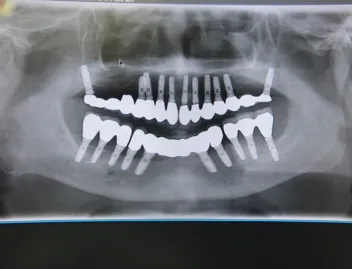

施術を検討されている方に様々なケースの施術前後の違いをご確認いただけるよう、インプラントやインビザラインでの矯正の症例を画像も用いて一覧にして載せております。「ずれている前歯を揃えたい」「受け口を直したい」「抜けた歯をキレイに整えたい」など、様々なご相談を承り、ご予算や仕上がりのご要望はもちろんのこと、長期的な口腔の健康維持も考慮したプランをご提案いたします。